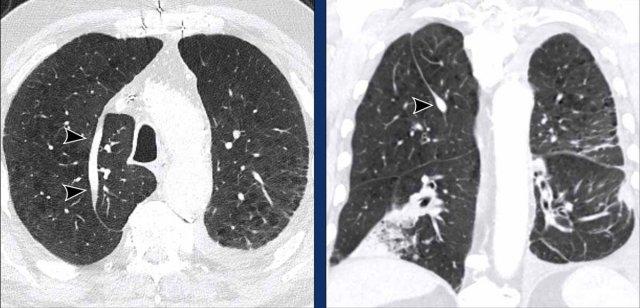

Hình ảnh

Phế quản khí quản phát hiện tình cờ ở nam giới 28 tuổi được chụp CT theo dõi ung thư (hình ảnh mặt cắt ngang), và ở nam giới 2 tuổi được chụp CT vì nhiễm trùng tái phát (hình ảnh mặt cắt vành).

Phế quản tim

Phế quản tim là một phế quản thừa thực sự, xuất phát đối diện với lỗ vào thùy trên phổi phải ở mặt trong của phế quản trung gian. Nó có thể thông khí cho một phần nhỏ nhu mô phổi, hoặc có thể là một cấu trúc tận cùng mù.

Bệnh nhân thường không có triệu chứng, mặc dù có thể xảy ra nhiễm trùng tái phát do thanh thải chất nhầy không đầy đủ.